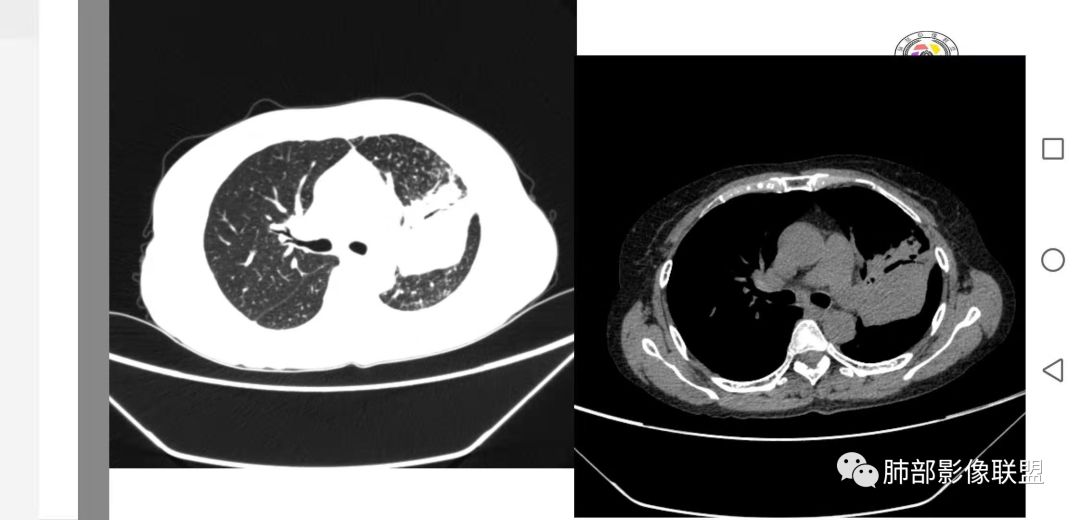

左肺病变支气管有狭窄后扩张,有部分钙化,符合结核,但叶间裂有膨隆,支气管有受压变窄表现,部分病灶内有血管,不能排除腺癌的可能,所以考虑肺结核合并腺癌可能

中年女性,慢性咳嗽,咳痰病史4个月,左肺上叶可见一团块状密度增高影,边界清,未跨叶裂,边缘有收缩有膨隆,周边可见结节影及树芽,周边部分小叶间隔增厚,内部可见点状坏死及血管包埋,有支气管充气征,部分支气管扩张,考虑淋巴瘤可能性大,鉴别结核

中年女性,咳嗽咳痰4月,加重半月。偶发热,肿瘤指标升高。病变主要位于左肺上叶后部,实变,病灶大部边缘平直、局部膨隆,邻近叶间裂局部向后膨隆,病变密度整体较均匀,见小斑片状低密度区及点状钙化影;左肺上叶舌段支气管可疑截断,病灶内支气管走形迂曲变形、不规则狭窄扩张、部分支气管内粘液栓形成,可见局部扩张支气管似小空洞相连,病灶内血管走形自然;糊墙。病灶前缘小叶间隔增厚,平滑;左肺下叶支气管管壁增厚,见部分树芽征及腺泡结节,边缘不清。纵膈及双肺门部分淋巴结钙化,隆突下淋巴结增大;未见胸腔积液。1.左肺上叶病灶倾向于恶性肿瘤,腺癌可能,排除粘液腺癌;2.左肺下叶少许炎症;

病灶整体有后坠感,小叶间隔增厚,这些用结核不容易解释,再加上肿瘤指标升高,所以把肿瘤放前面,炎症放后面。和左肺下叶病灶两元论。

晨读:左肺上叶实变,边缘不整,部分膨隆,其内支气管有狭窄有扩张,周围小叶间隔增厚,左肺下叶背段可见气腔结节,树芽征,边缘模糊,肺门及纵膈淋巴结钙化,考虑结核。鉴别肺炎型肺癌。

左上肺片状高密度影,其内有充气支气管征,血管造影征,叶间裂明显膨隆,支持粘液腺癌,鉴别于淋巴瘤、结核

中年女性,慢性咳嗽,右肺上叶块影,边缘膨隆+平直,肺容积略有缩小,部分支气管通畅、先狭窄后扩张,有树芽、网格,淋巴结钙化,强化轻,不均匀,内部低密度坏死,粘液栓,血管受累纤细,胸膜冠状位似有栽桩,良恶的特点皆有,首先考虑结核,肿瘤不敢排除,需要进一步结合临床

左上胸缩小,但是左上叶部分实变,边缘膨隆,内部有含气支气管,粘液栓,近端支气管堵塞

前端支气管通畅,部分稍扩张,走形自然

实变区支气管内粘液栓明显

上叶支气管堵塞处稍萎缩、凹陷,附近壁增厚,内可见小点状钙化

树芽征、小叶间隔增厚,淋巴结, 内部血管走形自然

分析:支气管粘液栓、支气管堵塞处萎缩、钙化,支气管通畅处部分扩张,树芽征——提示结核。

病灶膨隆明显,支气管堵塞,附近壁增厚,是否需要警惕恶性?